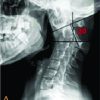

An 8-year-old female child presented with a 2-year history of a fixed elbow with almost no movement and a palpable bony mass. She had sustained significant trauma to her left elbow, followed by indigenous treatment in the form of native massage and slab for 2 months before the onset of symptoms [3]. Although it was her non-dominant limb, she had difficulties with daily activities such as clothing herself and tying shoelaces [4]. A clinical examination showed bony ankylosis and a fixed elbow with minimal range of movement at the elbow to be 0–10°. A palpable diffuse bony mass was present on the anterior aspect of the elbow, with the margins tapering to the corresponding muscles. No distal neurovascular compromise or limb length discrepancies were detected. Due to bone hyperplasia early during the disease, such masses may be mistaken for soft-tissue tumors or osteosarcomas. Soft-tissue tumors or osteosarcomas are often accompanied by periosteum hyperplasia, bone-cortex destruction, and unclear borders on X-ray radiography, which is not seen in this case. Thus, the mass was not a tumor (Fig. 1 and 2).